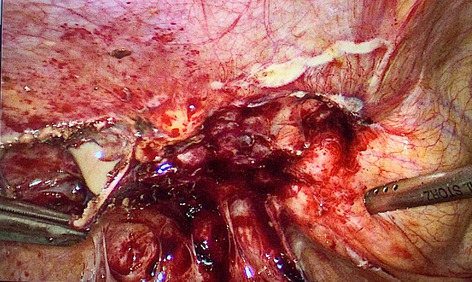

Introduction: Minimally invasive surgery and lately the usage of robotic technology has reduced the invasiveness of procedures, leading to improved patient outcomes after esophagectomy. The esophagogastric anastomosis represents a crucial step of the Ivor-Lewis procedure, as technical errors may lead to anastomotic leakage and severe postoperative morbidity. Anastomotic integrity is influenced by many different factors and there is great technical variety among surgeons. We have previously shown that a standardized 28-mm circular stapled anastomosis is very safe in Hybrid Minimally Invasive Esophagectomy. The aim of this study was to present and evaluate our standardized robotic circular stapled anastomotic technique in comparison to our large Hybrid patient collective.

Methods: Analysis of our prospectively collected, IRB approved database of hybrid, open, and robotic esophagectomies was performed. Starting 01/2019, we implemented an updated robotic standardized anastomotic technique using a circular stapler and ICG (indocyanine green) for our RAMIE cases at our academic center (Picture 1). Outcomes of patients undergoing this standardized robotic Ivor Lewis esophagectomy for esophageal cancer from 01/2019 – 11/2020 were compared to our overall cohort from 06/2016–06/2020 (Hybrid/Open group).Propensity score matching comparing robotic to hybrid procedures will be performed and data will be presented upon the meeting.

Results: A total of 615 patients were analyzed. A total of 96 patients underwent a robotic assisted Ivor Lewis esophagectomy. Of these, a total of 56 patients underwent a robotic thoracic reconstruction using the updated standardized circular stapled anastomosis. A total of 64 patients were operated using an open approach and 455 underwent a hybrid procedure with a circular stapled anastomosis (Hybrid/Open group). Demographic and oncological data is shown in Table 1. Mean age was 63 years (range 46–80) in the robotic group and 63 years (range 33–91) in the hybrid/open group. Further details about postoperative complications are depicted in Table 2. One patient developed an anastomotic leak in the robotic group, resulting in an anastomotic leak rate of 1.8%. In comparison 63 patients (12%) developed an anastomotic leak in the Hybrid/Open group (p = 0.0132). Median length of stay (LOS) was 13 days in the robotic group (range 7–52), compared to a median LOS of 15 days (range 9–99) in the open/hybrid group.